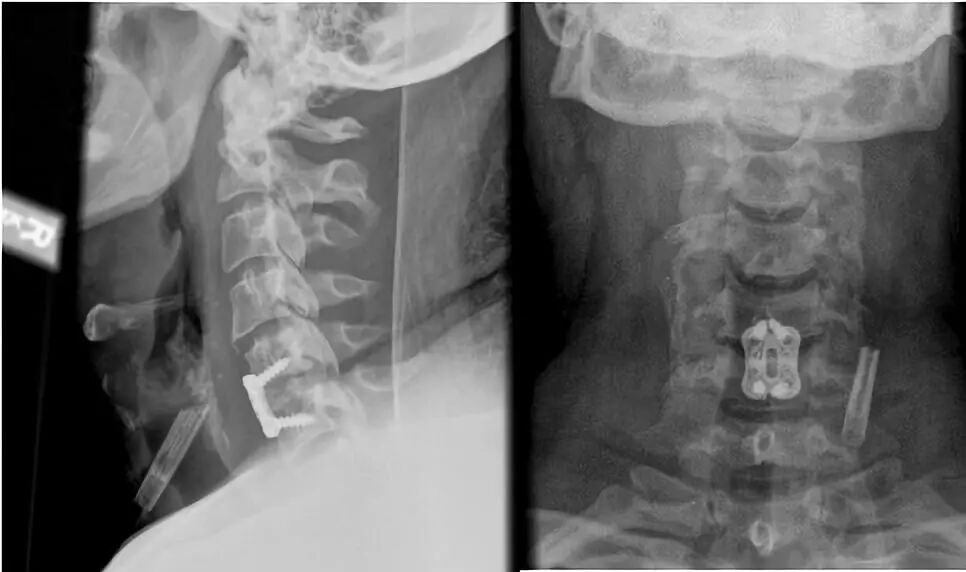

![]()

前板需选择适当的尺寸,避免过长延伸影响到相邻的椎间盘空间。

矢状面上将螺钉置于“发散”状态以使压力传递到椎间植入物上。

轴位平面上将螺钉内聚(“三角”)放置以防止拉出。

进行术中透视以确认前板、螺钉和椎间植入物的位置。